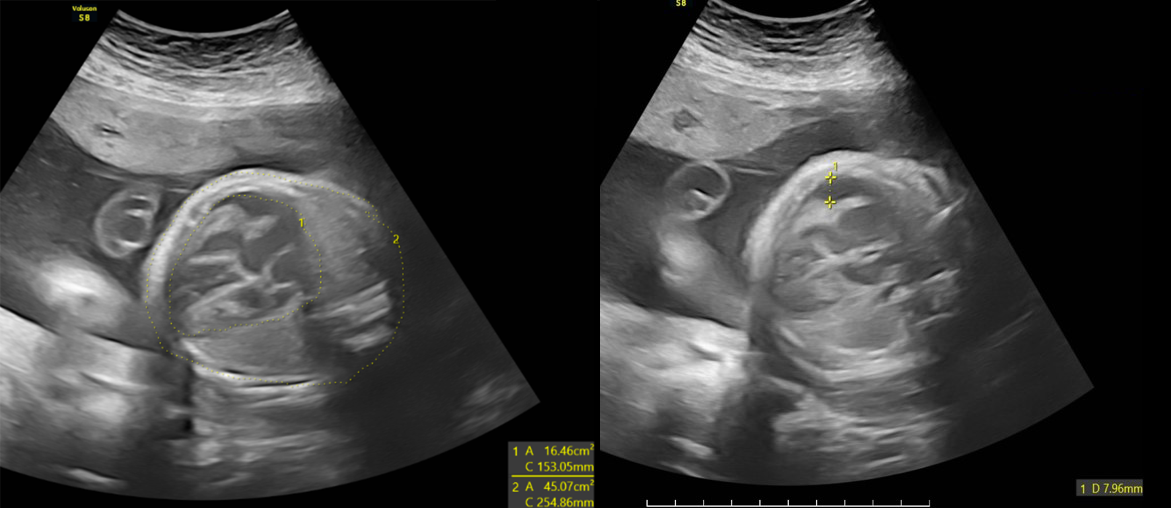

Hệ thống Y tế MEDLATEC vừa tiếp nhận một thai phụ trẻ đến khám thai. Kết quả siêu âm cho thấy tình trạng tim, gan, lách của thai nhi đều to bất thường, kèm giãn não thất hai bên và hố sau.

Tại đây, với thiết bị siêu âm hiện đại và đội ngũ bác sĩ chuyên môn cao, các dấu hiệu bất thường được kiểm tra, xác nhận chi tiết, bao gồm:

Những hình ảnh siêu âm này phản ánh mức độ nghiêm trọng của tình trạng nhiễm trùng thai nhi. Ngay sau khi thực hiện siêu âm, BSCKI. Trần Thế Quỳnh - Chuyên khoa Chẩn đoán hình ảnh, Phòng khám Đa khoa MEDLATEC Thanh Xuân - người trực tiếp thực hiện siêu âm trường hợp này đã thông báo chi tiết cho thai phụ về các bất thường, giải thích ý nghĩa của từng hình ảnh. Đây là những dấu hiệu tiên lượng nặng có thể gây nhiều biến chứng cho thai như bại não, điếc bẩm sinh... Kết quả hội chẩn cùng các bác sĩ tuyến trên, chị P. có chỉ định đình chỉ thai kỳ do tiên lượng xấu.